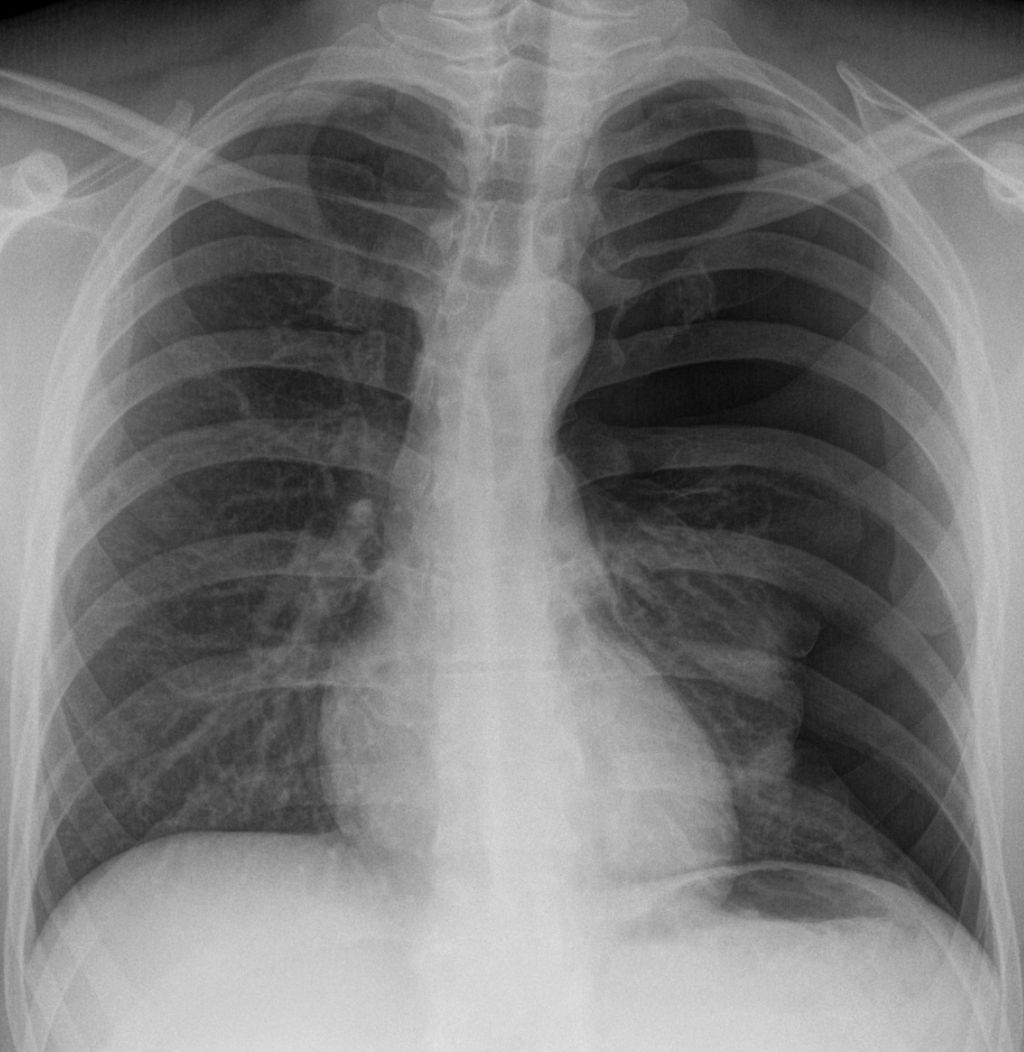

© wikipedia.org/Hellerhoff, CC BY-SA 3.0

Am besten lässt sich ein Pneumothorax im Röntgenthorax (in Expiration und Inspiration) oder im CT darstellen.

Nach Eingriffen wie Pleurapunktion oder Legen eines Subklavia-Katheters sollte immer eine Röntgen-Throaxaufnahme erfolgen, um einen iatrogenen Pneumothorax auszuschließen.